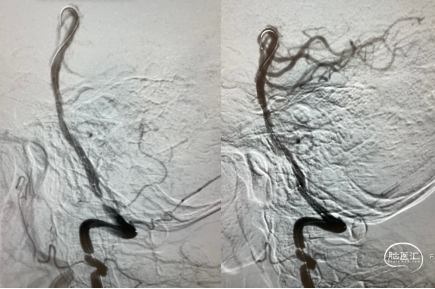

沿银蛇®DA送入PT导丝、微导管(Echelon-10)组合小心通过椎动脉V4段狭窄处,将导丝送至右侧大脑后动脉,为加强支撑,交换微导丝(Transend 0.014in x 300cm),撤出微导管。沿微导丝送入雷帕霉素药物洗脱椎动脉支架系统(3.0mm x 12mm)至狭窄处,准确定位,予7atm压力扩张后释放支架。

造影显示前向血流明显改善,支架贴壁良好,残余狭窄率约10%。